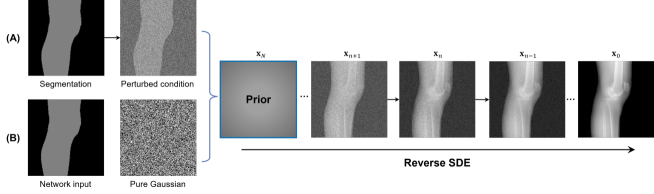

In this section, we provide qualitative and quantitative results of the two proposed diffusion-based methods and compare them with the baseline U-Net model. The first column of Fig. 3 showcases six randomly selected conditions: (a0)-(c0) show contour segmentations, and (d0)-(f0) denote segmentations containing contour and bones. In Fig. 3 (a1)-(f1), the images generated by U-Net contain blurred fine details in locations where bones overlap, despite maintaining the given shape, as highlighted by the red circle. In contrast, the results from CSM appear more realistic than the U-Net. However, their quality decreases with introduced constraints, as indicated by the red arrow in Fig. 3 (d2) and (f2). The results from CTM not only achieve nearly the same level of fineness as the labels but also provide reasonable results with respect to the given conditions as illustrated in the fourth column.

Table I summarizes the quantitative results averaged across all testing data. The evaluation metrics include mean absolute error (MAE) and peak signal-to-noise ratio (PSNR). We observed that CTM performs substantially better than U-Net and CSM under both segmentation-based conditions, and CSM performs worse than the U-Net.

Unlike the U-Net which learns a mapping function between input and output, the diffusion models can implicitly capture the underlying data distribution from the training data and then sample it, preventing the loss of fine details on the pixel level. However, in CSM, conditions are incorporated only at the first sampling step while being perturbed, which results in imprecise conditional information. Instead, CTM provides an estimated score function of the conditional distribution for each sampling step, accommodating both reliability and realism. Nonetheless, presently generated X-ray images only encompass independent 2D conditional information, which may introduce geometric inconsistencies between a set of projections. Future research will focus on modeling 3D probabilistic distributions with the provided 2D conditions to enable CT reconstruction from the generated projections. In addition, clinical datasets will also be incorporated.